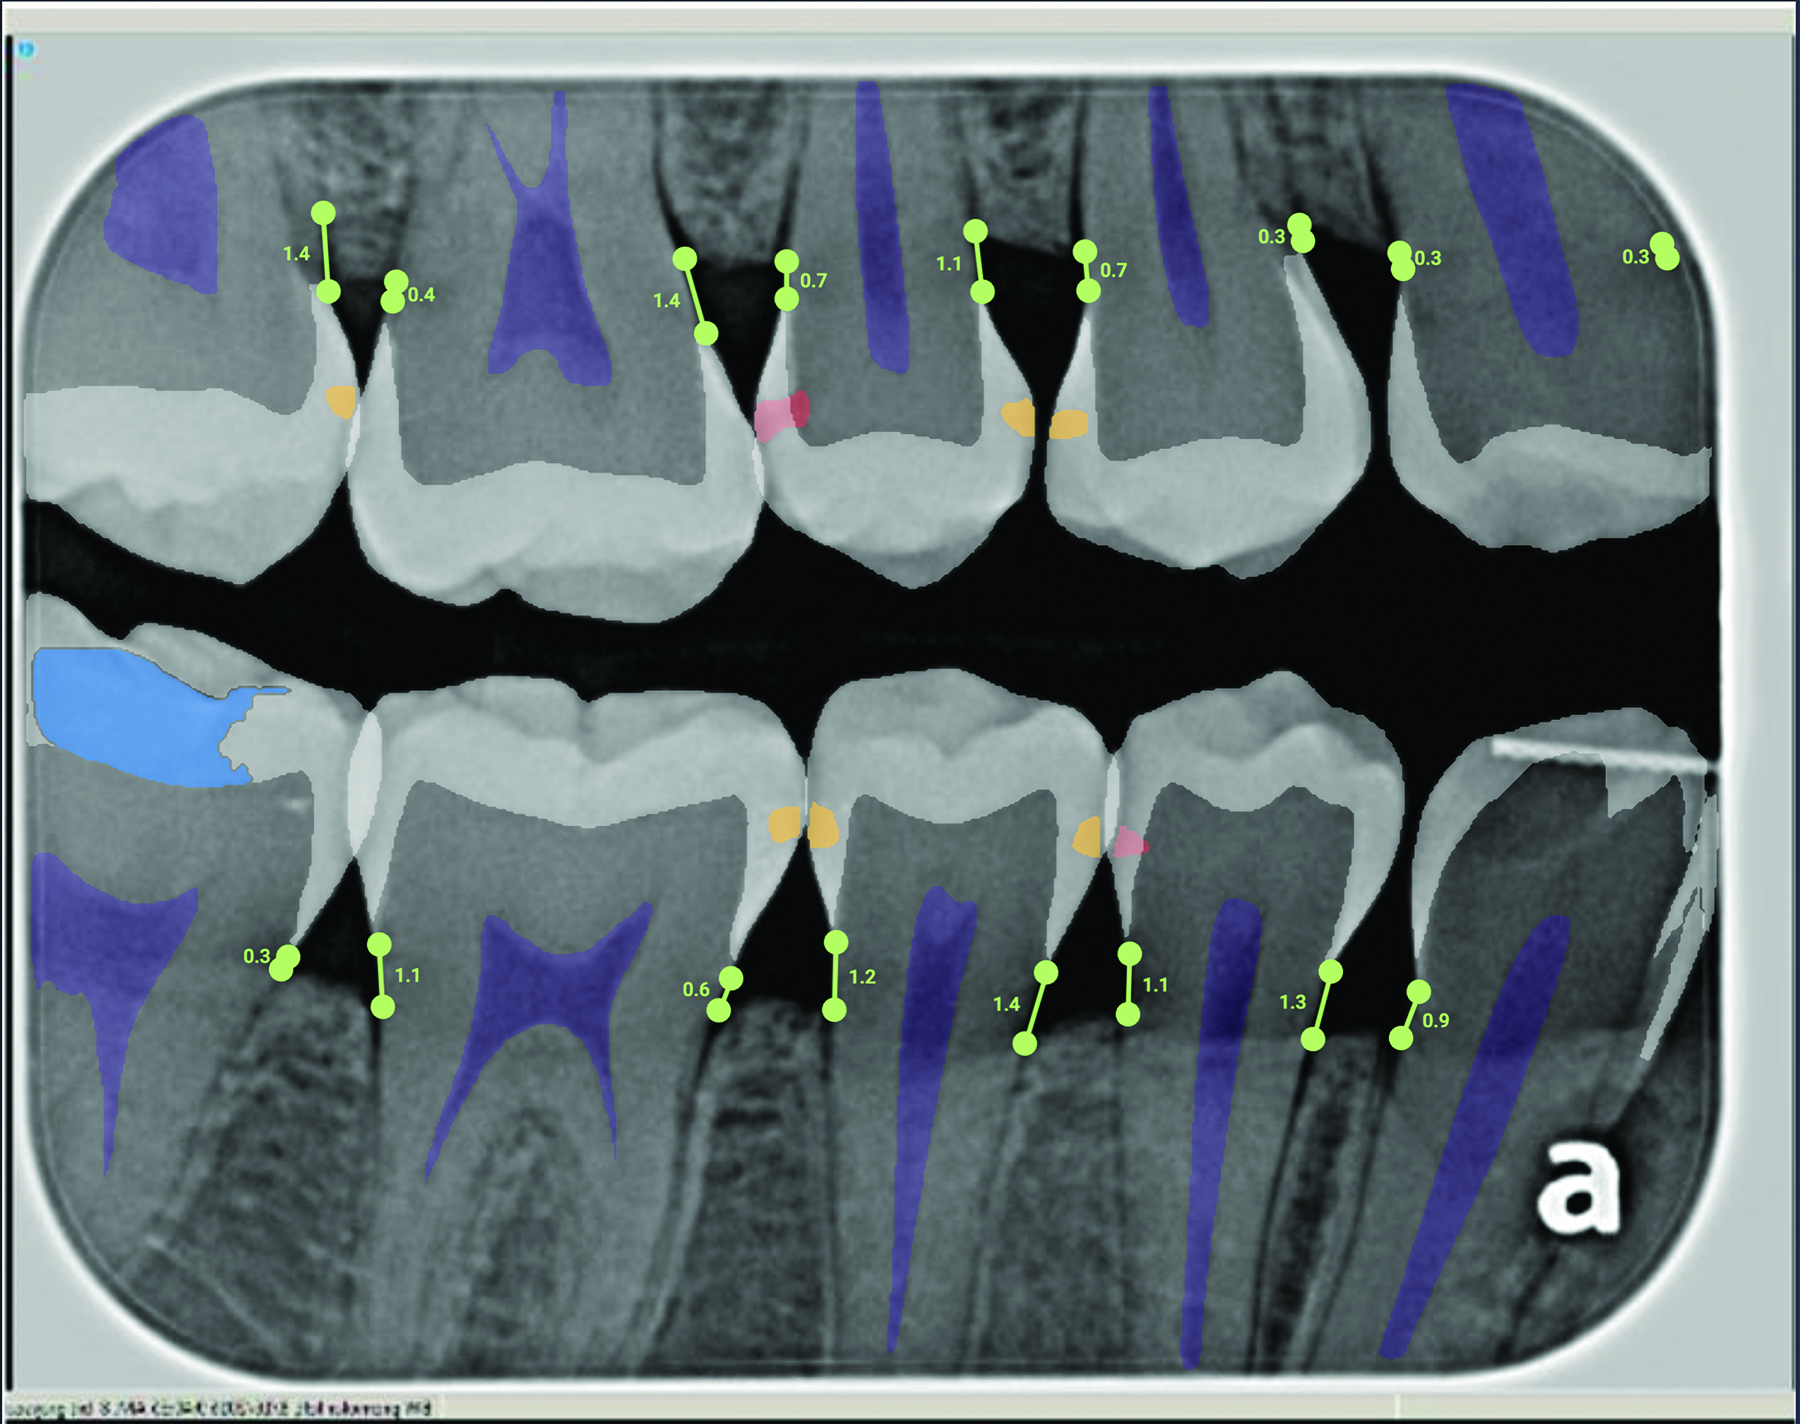

Radiation-based caries detection tools (ie, x-rays) are staples of dental practice. A new concept in radiation-based caries detection is artificial intelligence (AI) software that can overlay colorations on digital radiographs to indicate areas of radiolucency indicative of demineralization and dental caries (Figure 4). The sensitivity (true positives) of AI relative to a consensus of experts is 73% to 90% and specificity (false negatives) is 61.5% to 93%.48 Therefore, AI is only a tool to aid the dentist in identifying potential lesions. AI analysis is most useful for increasing sensitivity for identifying enamel-based caries. A study determined that AI detection of enamel caries increased the use of preventive treatments but also increased the occurrence of invasive treatment.49

Fig 4. Artificial intelligence (AI) caries detection demonstrating several incipient enamel lesions.

Figure 4